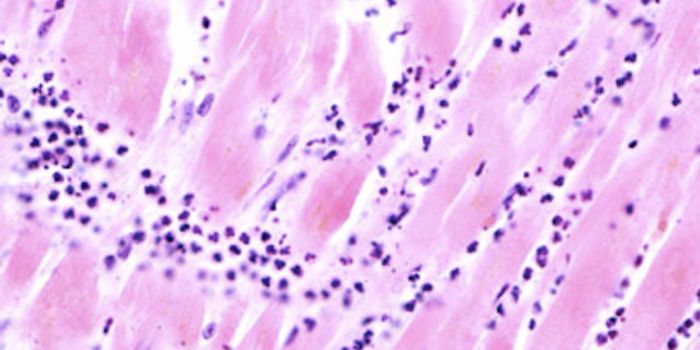

JAN 20, 2022CardiologyNew research has shown changes to heart muscle tissue in patients who died of COVID-19.

APR 04, 2016Health & MedicineViral infections that make their way into the heart can cause a spectrum of damage to the cardiovascular system, dependi ...